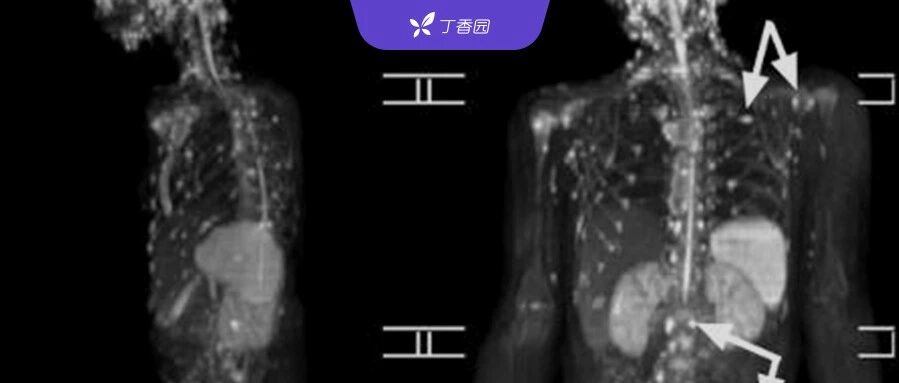

| 9 岁女孩全身骨骼异常,多家医院怀疑恶性肿瘤,病因却在猫身上找到了 | 查看 | 2024-04-06 20:00:19 | 46482 | 63 | 2024-04-06 21:03:31 | 丁香园 | |